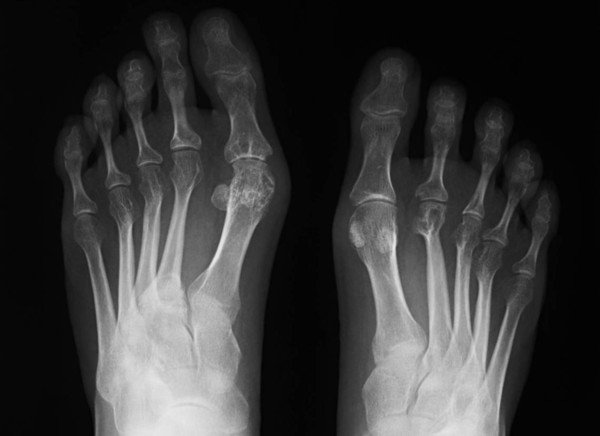

Svar: Det är inte helt klarlagt varför artros uppstår, och det finns sannolikt olika orsaker till småleds- respektive storledsartros. Sjukdomen är delvis en del av det normala åldrandet, men den kan förvärras tidigare genom trauma på leden och överbelastning. Den artrotiska leden karaktäriseras av nedbrytning av glidytan i leden, minskad ledspringa, förtätning av den underliggande benplattan och nybildning av ben i ledkanterna. De viktigaste åtgärderna för att minska besvär är fysisk aktivitet, särskilt träning av den drabbade ledens omgivande muskulatur, och viktnedgång. Som komplement används ibland smärtstillande läkemedel, oftast paracetamol. Forskningen kring artrosmekanismer har gått framåt senaste åren, och kliniska prövningar pågår av flera nyare läkemedel, som specifikt blockerar vävnadsnedbrytande ämnen. Vissa patienter har svårare smärta och smärta i vila, vilket tillsammans med gravt förstörd led kan vara indikation för operation med knä- eller höftplastik. Glukosamin, som många patienter tar mot artros, har i studier tyvärr inte visat bättre symtomatisk effekt än sockerpiller och rekommenderas därför inte av Socialstyrelsen.